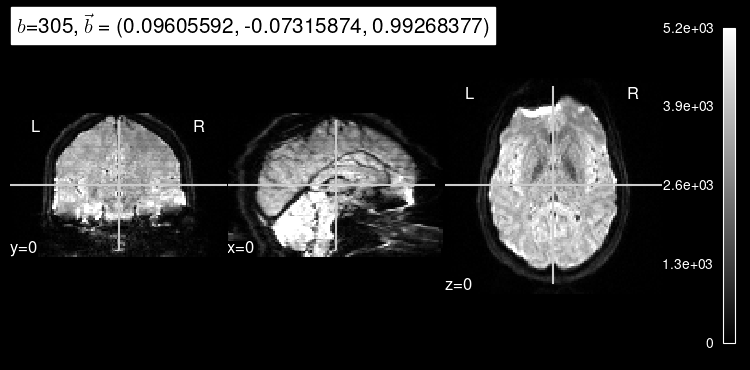

plot_dwi(predicted, dmri_dataset.affine, gradient=data_test[1]);

As expected, the b=0 doesn’t look very much like the particular left-out direction, but it is a start!